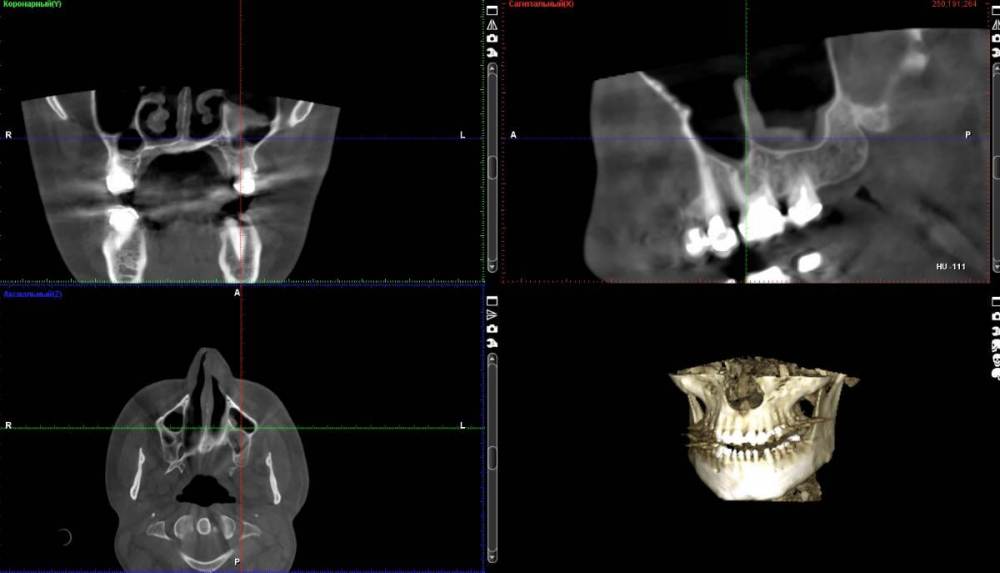

neumann Опубликовано 24 марта, 2022 Поделиться Опубликовано 24 марта, 2022 Добрый день. После перелечивания каналов 6 зуба появились неприятные ощущения в пазухе и слева от глаза. Сделали КТ и вот что оно показало. Нужно ли бить тревогу (см. указатель) или в этом нет ничего страшного? На что еще нужно обратить внимание? Спасибо. Ссылка на комментарий

neumann Опубликовано 24 марта, 2022 Автор Поделиться Опубликовано 24 марта, 2022 @Женька спасибо за ответ. вот такие срезы? Ссылка на комментарий

Женька Опубликовано 24 марта, 2022 Поделиться Опубликовано 24 марта, 2022 @neumann уже что-то теперь нужны срезы именно "вокруг" этого зуба На первый взгляд это просто анатомическое образование. Так называемая септа (перегородка) в верхнечелюстной пазухе. И повода для беспокойства нет (если судить именно по тем срезам что Вы предоставили. Ссылка на комментарий